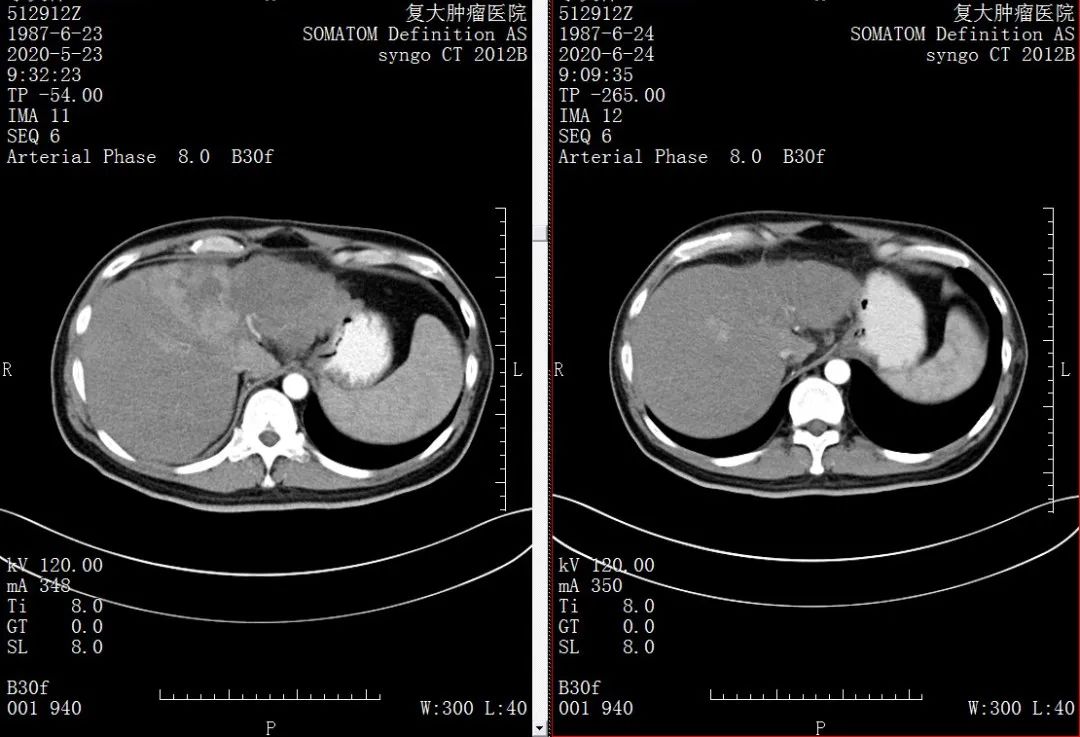

肝癌就真的不能治了吗?“李先生来我院时肝左叶全是肿瘤,已经侵犯到肝右叶,只有一小块是好的,甲胎蛋白指数高达8872IU/ml(参考值0~5.8),属于原发性肝癌晚期。“杨清峰主任解释道,针对李先生的病情,经过科内讨论后,为进一步降低肿瘤负荷,提高生活质量,以期改善生存期,给予肝癌持续性肝动脉灌注化疗术为李先生治疗。第一次灌注治疗后肝左叶的大部分肿瘤已坏死,肝右叶还有活性,甲胎蛋白降到1891IU/ml;第二次灌注治疗后甲胎蛋白指数已经降到了443IU/ml。

△第一次、第二次介入治疗后

“经过两次肝癌持续性肝动脉灌注化疗,患者的情况已经得到基本控制,绝大部分肿瘤已经坏死,有希望延长李先生的生存期。”杨清峰主任告诉我们,李先生这个治疗效果比预期的要高很多,可以说是个奇迹。